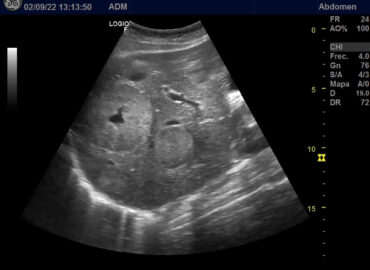

Paciente de 32 años secundigesta, nulípara AMED: Tratamiento con Isotretinoina (suspendido 2 meses previos al diagnóstico de embarazo) APP: […]